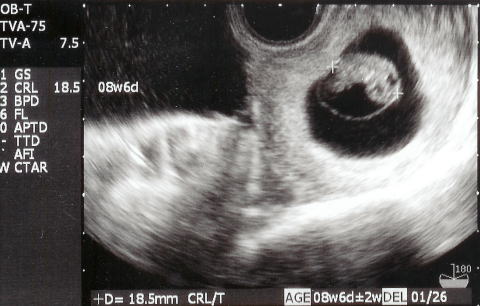

|  |  今日は健診です。依亜を幼稚園へ送った後、恭子お姉ちゃんとももちゃんも一緒に、電車で産院へ向かいました。30〜40分待ち診察。順調でしたが、ママは生理不順のため、排卵が遅れたということで、出産予定日が1/20から1/26に変更となりました。makotoの出産予定日は来年1月26日です。